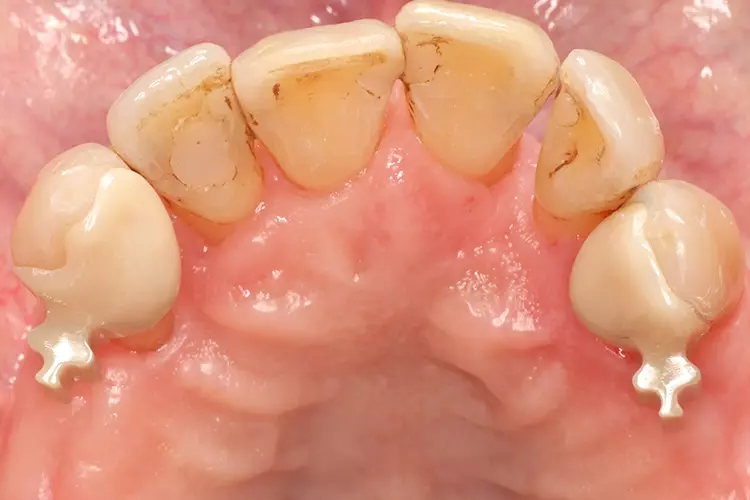

Als relative Kontraindikation sind karies- und restaurationsfreie Pfeilerzähne mit zervikalen keilförmigen Defekten über 1 mm Tiefe zu nennen, da diese zu einer erhöhten Frakturgefahr des Pfeilerzahnes bei Belastung führen. Adhäsivattachments können zur Reparatur vorhandener Doppelkronen- oder Geschiebearbeiten verwendet werden, sofern der verbliebene Nachbarzahn einer verloren gegangenen Doppelkrone karies- und restaurationsfrei ist. Die Matrize wird in diesem Fall in die ausgeschliffene Doppelkrone oder in die Geschiebekrone des verlorenen Pfeilerzahns eingeklebt (Abb. 1 bis 4).